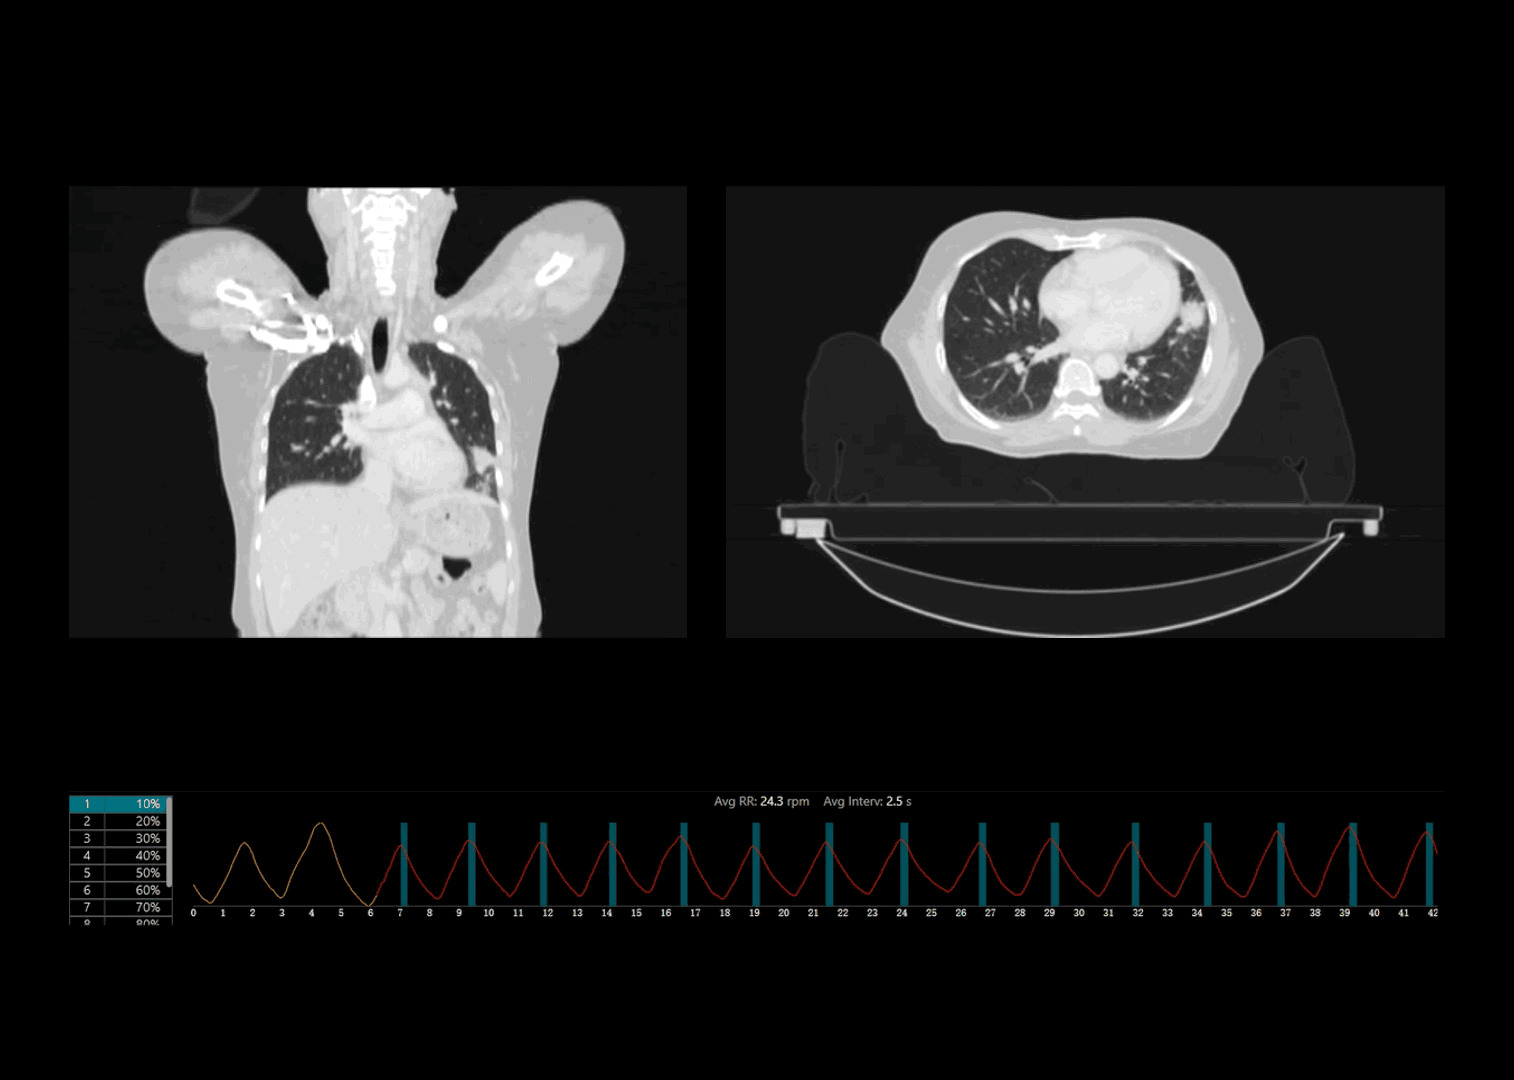

运动器官动态追踪

支持前瞻式断层扫描、前瞻式螺旋扫描和回顾式螺旋扫描,应对各类放疗应用场景

联影自研压力传感式呼吸门控系统精准记录规律呼吸、咳嗽异常等各类临床场景下的呼吸信号

基于实际呼吸频率情况自适应推荐最佳螺距参数,相较于传统固定螺距采集,有效减少图像运动伪影

超快机架转速结合球管超长连续曝光能力,采集范围相较传统大孔径CT系统提升2倍*,覆盖各类临床应用场景